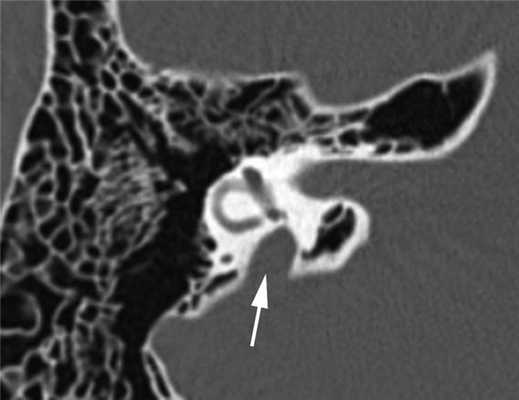

Диагностика. СРВП часто мимикрирует заболевания среднего уха. Известно, что аномальное соединение внутреннего уха с подоболочечным пространством головного мозга, также как и «третье окно» лабиринта, может давать костно-воздушный разрыв на аудиограмме, более выраженный на низких частотах. Это явление описано в англоязычной литературе как интралабиринтная кондуктивная тугоухость, «псевдокондуктивная» тугоухость или «ложная» кондуктивная тугоухость [18]. Поэтому любое снижение слуха, характеризующееся нормальными тимпанограммами типа А, наличием акустических рефлексов и костно-воздушного интервала, более выраженного на низких частотах, должно вызывать подозрение на аномалию внутреннего уха. В таких случаях показано проведение высокоразрешающей мультиспиральной КТ височных костей, что позволит избежать эксплоративной тимпанотомии, проводимой ошибочно по поводу смешанной или кондуктивной тугоухости неясного генеза. На К.Т. данный синдром характеризуется расширением водопровода преддверия от 1,5 до 5—6 мм (рис. 2).

Рис. 2. Широкий водопровод преддверия (стрелка). Компьютерная томограмма правой височной кости в аксиальной проекции. Пациент А., 14 лет.

1. Пациент А., 14 лет (аудиограмма, рис. 4), наблюдается в отделении нефрологии Научного центра здоровья детей с диагнозом: нефротический синдром, дистальный почечный тубулярный ацидоз. Снижение слуха возникло внезапно, без видимых причин, в возрасте 13 лет 6 мес. На компьютерной томограмме височных костей — двустороннее расширение водопровода преддверия (см. рис. 2). Высокоразрешающая МРТ пирамид височной кости также выявила широкий водопровод преддверия (см. рис. 3). Рекомендовано использование системы BICROS.